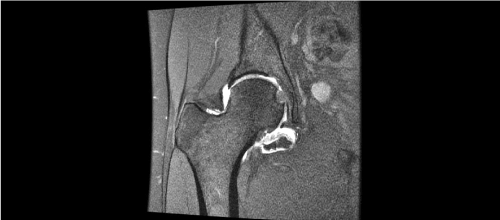

Figure 2a. Coronal T1-Wieghted image (Left)

Figure 2b. Axial T1-Wieghted image (Right) showing hyperintense masses highly suggesting of synovial chondromatosis of right hip